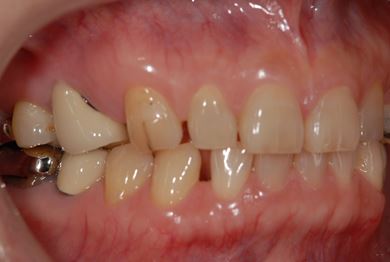

インプラントの症例写真 IMPLANT

インプラント治療

| 主訴 | 乳歯がぐらついている。 | ||||||||||||||||||||||||||||||||

| 治療方針 | インプラント治療にて、機能的・審美的回復を行う。 | ||||||||||||||||||||||||||||||||

| 治療内容 | インプラント1本、メタルボンドセラミッククラウン1本 | ||||||||||||||||||||||||||||||||